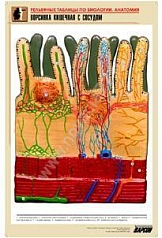

11. Ворсинка кишечная с сосудом;

Изделие соответствует Перечню средств обучения и воспитания, утвержденному Приказом Минобрнауки России N 804 (подраздел «Демонстрационные учебно-наглядные пособия для профильного медико-биологического класса»).